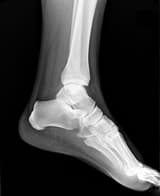

“My visits to orthopaedic surgeons started as soon as I got back home. I visited doctor after doctor — varying diagnosis, varying perceptions, most of them showed doubt about me recovering within six months and I was told that even if I did recover, the chances of me being able to survive the rigorous training at the Academy were very bleak.

“I ran from doctor to doctor, searching for the ‘perfect’ one who would cure me completely within six months and make sure I got though the training. However, with every visit, my confidence began dropping, my pain started intensifying and my dreams were slowly going up in thin air as I realised that I was so near but yet so far from reaching my goal.

“I visited the doctor along with my mother and was immediately struck by his warmth, his serene, calm and composed nature. He told me to put all my x-rays, MRIs and other medical records aside and asked me a simple question — ‘Are you willing to do what you have to do to heal yourself?’

“At the first session, I was asked to close my eyes, calm myself down and follow a mental process. We started concentrating on each and every part of my body — throwing a divine healing light and illuminating it, then using the prāna of the universe to spread energy across the body to revitalise it and believe in its immense God-given potential to work miraculously. Once the divine light had been spread to each and every part, we then came down to the foot which was broken.

“I was told to treat the foot like a small child and give it the love which an innocent little baby deserves. We then went deep into the foot by opening it mentally and understanding what exactly was present inside — the portion which was broken seemed like a black patch. I was asked to spread the divine light over the patch and remove the black portion, to talk to my foot and comfort it, understand what it exactly wanted.